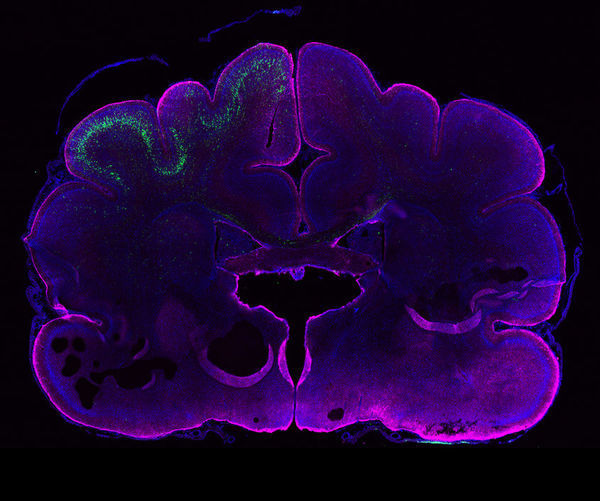

Building a bigger brain

"The human brain owes its characteristic wrinkled appearance to its outer layer, the cerebral cortex. During human evolution, the neocortex, the evolutionarily youngest part of the cerebral cortex, expanded dramatically and had to fold into wrinkles to fit inside the restricted space of the skull. The human neocortex supports advanced cognitive skills such as reasoning and language. But how did the human neocortex become so big? The answer may lie in genes that are unique to humans, such as ARHGAP11B. Researchers at the Max Planck Institute of Molecular Cell Biology and Genetics in Dresden found that this human-specific gene, when introduced into the developing brain of ferrets, can cause an enlargement of their neocortex." [...]